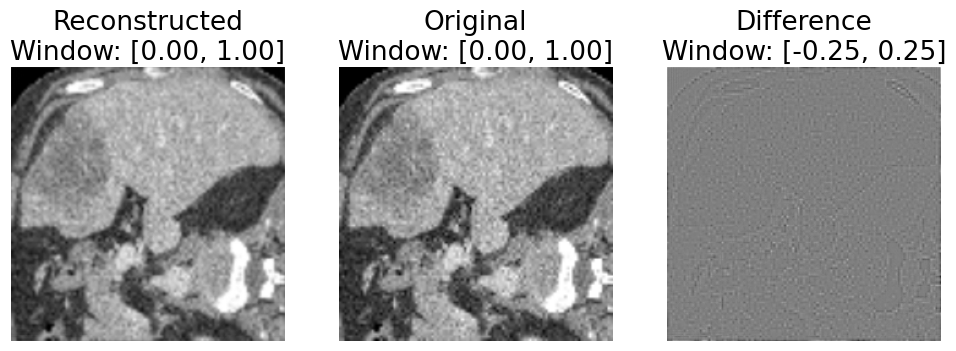

Figure 2. Reconstruction error example (first image is RR, second image is OO). A difference is visible between the original image and the result after forward projection and backprojection.

Refer to caption

Figure 3. Unintended reconstruction error mixed with intended simulated ring artifact (first image is RdistortedR_{distorted}). For ease of visualization, we simulate 5 adjacent detector channels with gain error -10%.

We observe a notable “reconstruction error” introduced by our simulation approach. In particular, when considering discrete images, the result of performing forward projection followed by backprojection is not equivalent to the original image, as seen in Fig. 2. We were not able to mitigate this error by increasing the number of projection samples to increase the sampling resolution for the transform. We believe this may be a consequence of using relatively small images with far fewer samples than can be obtained with a real CT scanner and a physical volume. Unfortunately, with our approach, this unintended reconstruction error becomes mixed with the intentional simulated distortions we apply in sinogram space (Fig. 3), muddying the conclusions which can be drawn regarding domain adaptation.